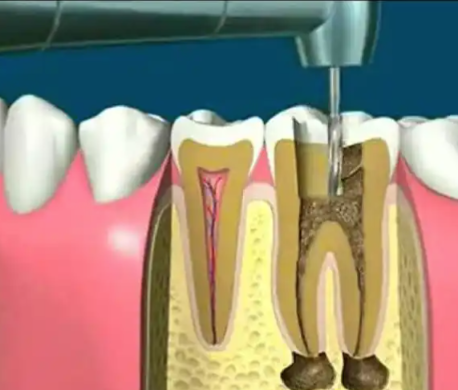

根管治疗:作为医院重点项目,针对牙髓感染或牙齿损伤患者,采用热牙胶充填设备等精良技术,精细清除感染牙髓,有效修复牙齿功能,防止感染扩散,诊疗成效有保护。